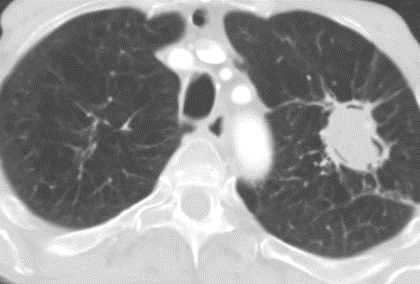

CT scan showed a cavitating lesion in the left upper lobe with a filling defect in the middle. Appearances suggestive of an aspergilloma. Patient became unstable due to large volume of haemoptysis.